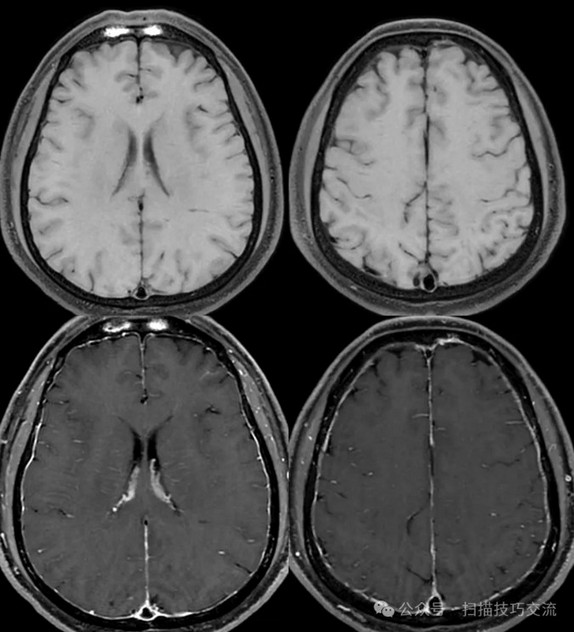

•汗腺分泌:正常,皮肤划痕正常反应。 •尿便障碍:无。性功能障碍无。 •专科情况:正常。不逐一罗列。 •辅助检查:01-05颅脑CT提示:1,上矢状窦、双侧横窦密度较高,请结合临床,必要时进一步检查;2,双侧脑室后角可疑稍高密度影,右顶叶局部脑沟密度可疑增高,建议进一步检查。 •初步诊断:静脉窦血栓

临床申请:颅脑平扫,静脉成像,磁敏感成像,颅内静脉血管黑血成像。

图像不逐一罗列,未见异常。

SWAN未见异常。

PC-MRV未见异常。

颅内静脉黑血成像,CUBE T1fs w/o +c,静脉窦未见异常。